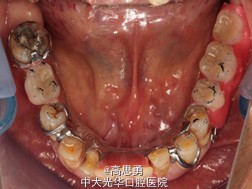

修复科第二次就诊口内检查:

11、12、13、21、22、23、33、42、43、44牙颈部见黄色充填物

13 探(-)、叩(-)、松(-),HE面见白色暂封物

口腔卫生状况尚可、牙石少,其余牙叩(-)、松(-)